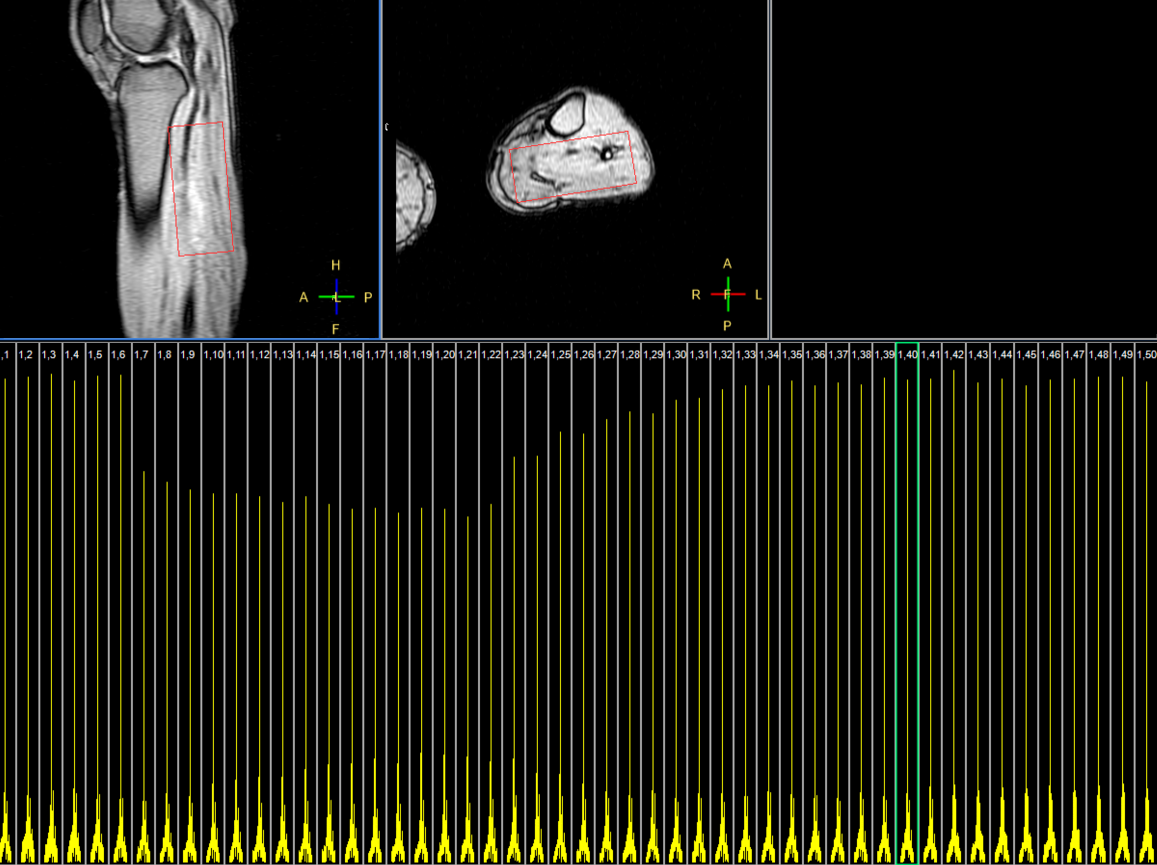

31P Phase Acquired

31P Phase Acquired (5 sec/acq, 50 dynamics)

31P Phase Acquired (Rest - Stress - Recovery)